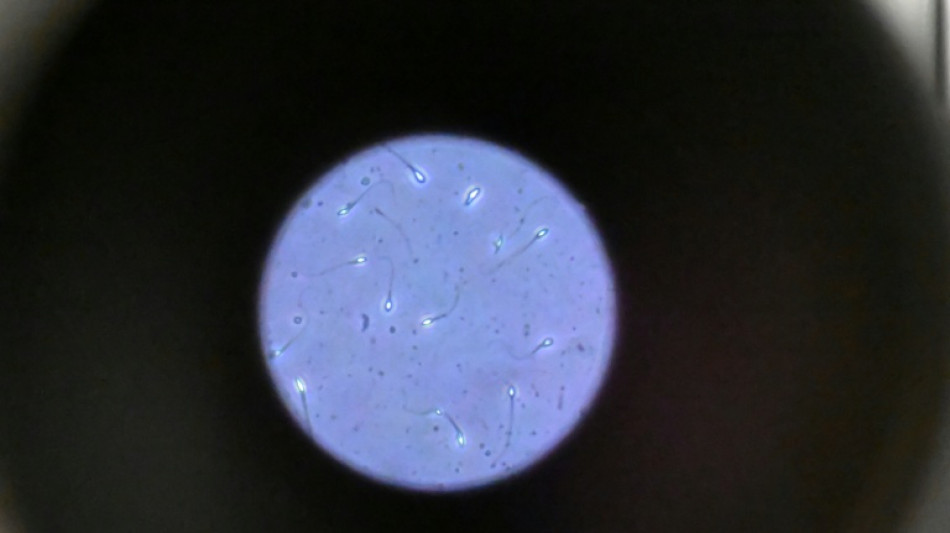

Les chercheurs ont testé successivement du sperme de souris et humain dans ce dispositif placé dans un appareil en constante rotation pour simuler la microgravité.

Les gamètes ont été environ 50 % moins performants pour naviguer à travers ce parcours que sous la gravité terrestre. Cela équivaut à une baisse de 30% du taux de fécondation réussie, selon les résultats de l'étude.